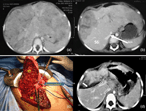

Monosegmental ALPPS: a long-term survival alternative to liver transplant in PRETEXT IV hepatoblastoma

Eloy Francisco Ruiz Figueroa and others

Journal of Surgical Case Reports, Volume 2019, Issue 5, May 2019, rjz144, https://doi.org/10.1093/jscr/rjz144